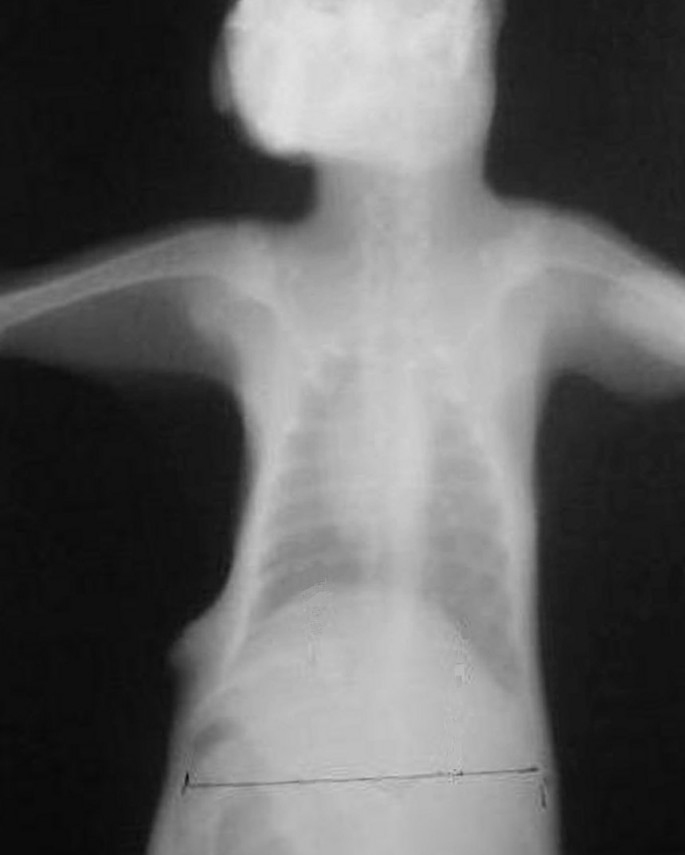

The mean preoperative and postoperative 7th day measurements of diaphragmatic heights are shown in Table 1 for both groups. The mean right hemidiaphragmatic elevations were 7.0 ± 2.5 in BTX-A (Figure 1) and 1.3 ± 1.2 in control (Figure 2) groups. Diaphragmatic elevations were significantly different (p = 0.0035) between groups. Fluoroscopic examination of diaphragmatic movements revealed that paralyses reversed in 8–12 weeks.

After the surgery, the rabbits were closely monitored for clinical evidence of pain (vocalisation, tachypnea, and restlessness) for seven days. Chest radiographs were taken for evaluation of diaphragmatic elevation, residual air space and complications. X-rays were taken during in inspiration. Since the onset of paralytic effect of Botulinum toxin type A begins in 2nd day, diaphragmatic elevation was evaluated radiographically in four consecutive antero-posterior-chest radiographs (preoperatively, postoperatively, 3rd and 7th day). All the roentgenograms were taken at a 90 cm distance from the cassette while animals were in erect position. Diaphragmatic elevation was measured as a distance in millimetre from the line connecting the 10th ribs to the midpoint of the right hemidiaphram. Reversal of paralysis was observed by fluoroscopic examination of diaphragmatic movements.